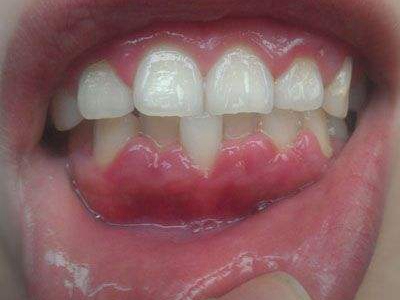

慢性龈炎又称边缘性龈炎或单纯性龈炎,主要表现为游离龈和龈乳头因炎性水肿,而变为鲜红或暗红色,龈缘变厚,龈乳头圆钝肥大。慢性龈炎的患病率高,治愈后仍可复发,部分患者可发展成为牙周炎。

慢性龈炎的病损部位一般局限于游离龈和龈乳头,以前牙区为主,尤其以下前牙区最为显著,患者常因刷牙或咬硬物时牙龈出血而就诊。游离龈和龈乳头颜色变为鲜红或暗红色,病变较重时炎性充血可波及附着龈。龈缘变厚,龈乳头圆钝肥大,可增生呈球状,覆盖牙面。牙龈松软脆弱,缺乏弹性。

当牙龈以增生性反应为主时,龈缘和龈乳头呈坚韧的实质性肥大,质地较硬而有弹性。龈沟液量增多,还可能出现龈沟溢脓现象。